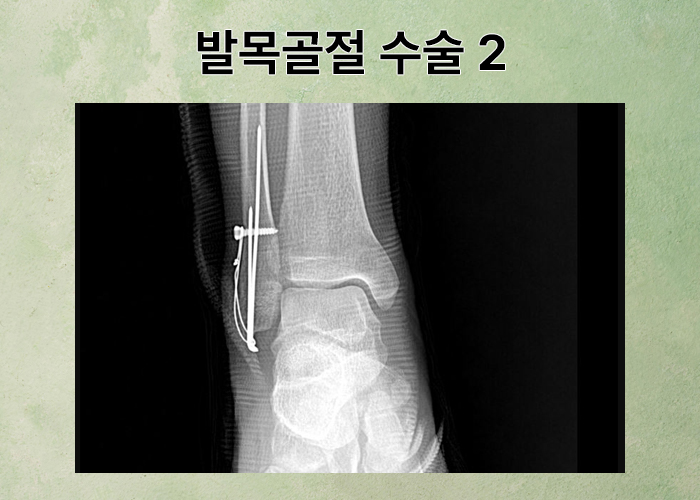

발목 부근이 부어 오르며 심한 통증을 호소하셨고 김@@님은 응급실로 내원하여 정밀 검사를 받게 되었습니다. 검사 결과, 발목과 종골의 골절 진단받아 수술적 치료가 불가피 했는데요,

의뢰인은 복사뼈 골절로 수술하였고 향후 발목 움직임이 제한되는 운동 장해가 예상되었습니다. 의뢰인의 신체에 잔존한 장해에 대해 대학병원 전문의로부터 맥브라이드 방식의 장해 평가를 도와드렸고 평가된 장해를 기초로 의뢰인의 나이, 임금, 과실을 고려하여 상실수익액을 계산할 수 있었습니다.